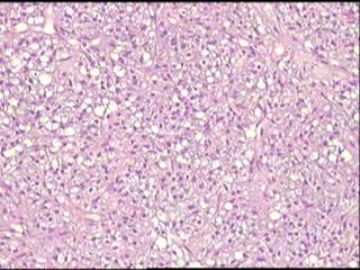

•25岁,女性,停经35周,发现腹腔包块1月余。

•手术所见:右侧卵巢肿瘤,12×8.6×8.0cm大小,表面光滑,内实质似鱼肉样、部分区域胶冻状,伴少许盆腔积水。

• 卵巢肿瘤图3

图3

硬化性间质瘤